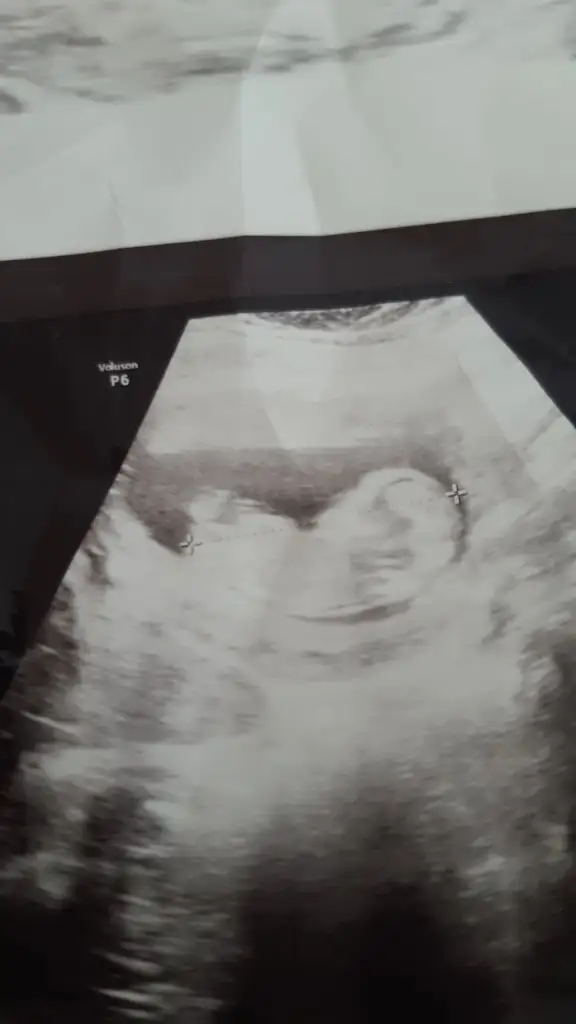

Büyük ihtimalle erkek canım sağlıcakla hayırla kucağına almak nasip olsunKızlar iyi akşamlar ultrason görüntüsüne göre cinsiyet tahmini yapabilir misiniz :) En net görüntümüz buydu. 12 haftalıkken. Şuan 15 haftalığız haftaya doktora gidicez. Merak ediyorum:) Her ne olursa olsun sağlıkla gelsin tabiki. Teşekkürler

Yüzde yüz milyon erkek besbelli canım benim oğlumun da böyleydi ultrason görüntüleriKızlar benimkine bakar mısınız? Eki Görüntüle 2898157